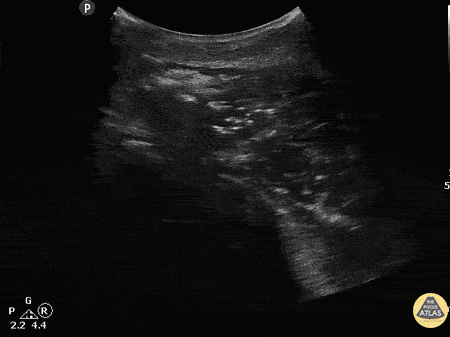

A patient with past medical history of diabetes presented with atraumatic right shoulder pain. Physical exam revealed decreased range of motion without obvious superficial abnormality. The patient was noted to be febrile and tachycardic. A curvilinear ultrasound reveals extensive air (scattered punctate hyperechoic areas) throughout the deltoid muscle indicative of infectious myonecrosis. Image courtesy of Robert Jones DO, FACEP @RJonesSonoEM Director, Emergency Ultrasound; MetroHealth Medical Center; Professor, Case Western Reserve Medical School, Cleveland, OH View his original post here